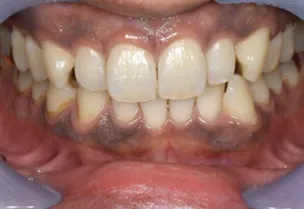

患者様のQOL向上を目指し、歯を残す治療を提供しています。

歯を残す治療や予防にも力を入れており、小さなお子様にも対応している歯科のため、年齢を問わずにお気軽にご相談いただけます。